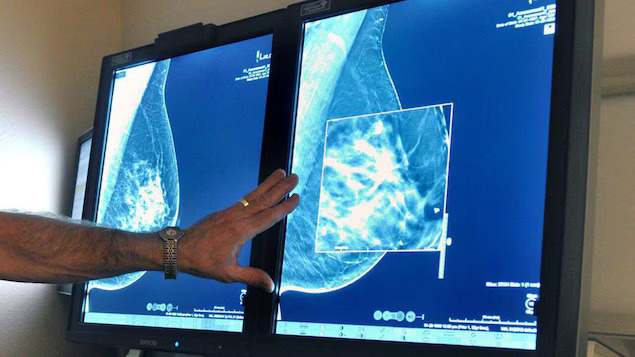

கனடாவில் மார்பகப் புற்று நோய் தொடர்பில் விசேட அறிவிப்பு வெளியிடப்பட்டுள்ளது.

கனடாவின் அனைத்து மாகாணங்களும் பிராந்தியங்களும் மார்கப் புற்று நோய் குறித்த பரிசோதனைகளை 40 வயதிலிருந்து மேற்கொள்ள வேண்டுமென அறிவுறுத்தப்பட்டுள்ளது.

கனடிய புற்று நோய் அமைப்பு இந்த அறிவுறுத்தலை வழங்கியுள்ளது. சில மாகாணங்களில் 40 வயதிற்கு மேற்பட்டவர்களிடமிருந்து மமாகிராம்ஸ் பரிசோதனை நடத்தப்படுகின்றன.

தற்பொழுது அநேகமான பகுதியில் 50 வயதுக்கும் மேற்பட்டவர்களிடம் மார்கப் புற்று நோய் பரிசோதனை மேற்கொள்ளப்படுகின்றது.

நாடு முழுவதிலும் உள்ள பெண்கள் மார்கப் புற்று நோய் பரிசோதனை செய்து கொள்ள சமசந்தர்ப்பம் வழங்கப்பட வேண்டுமென கோரிக்கை விடுக்கப்பட்டுள்ளது.

ஆரம்பத்தில் அடையாளம் காணுவதன் மூலம் எளிமையான வழிகளில் சிகிச்சை அளிக்கப்பட முடியும் என புற்று நோய் அமைப்பு அறிவித்துள்ளது.